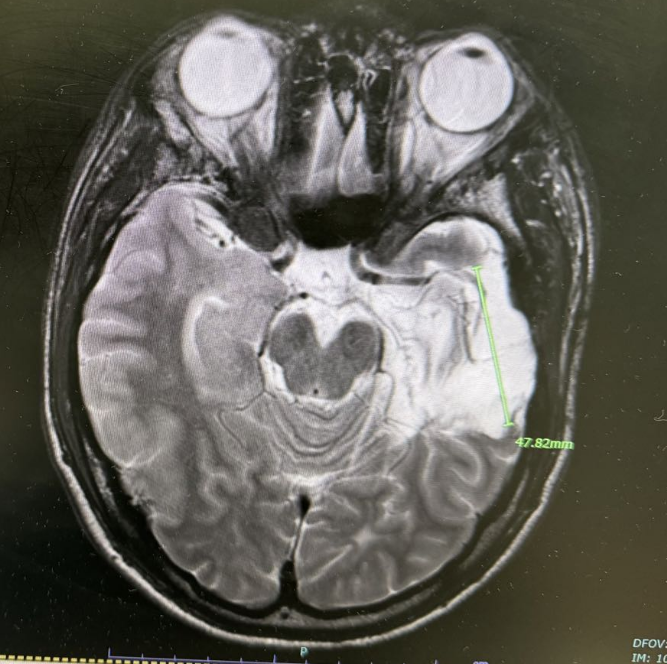

这是一台脑动脉瘤手术,通过术前影像、术中精细梳理,很快找到了动脉瘤,再通过多次的试夹闭,保留了穿支血管。

1、将自己在日本学习研修的所见所闻,尤其是功能区肿瘤的全程化管理应用于临床工作实践中;同时在神经内镜技术方面,积极提高了神经内镜治疗疾病谱,从单纯的颅脑外伤、脑出血手术,转型为神经内镜下微创技术进行治疗,提高了患者的疗效。